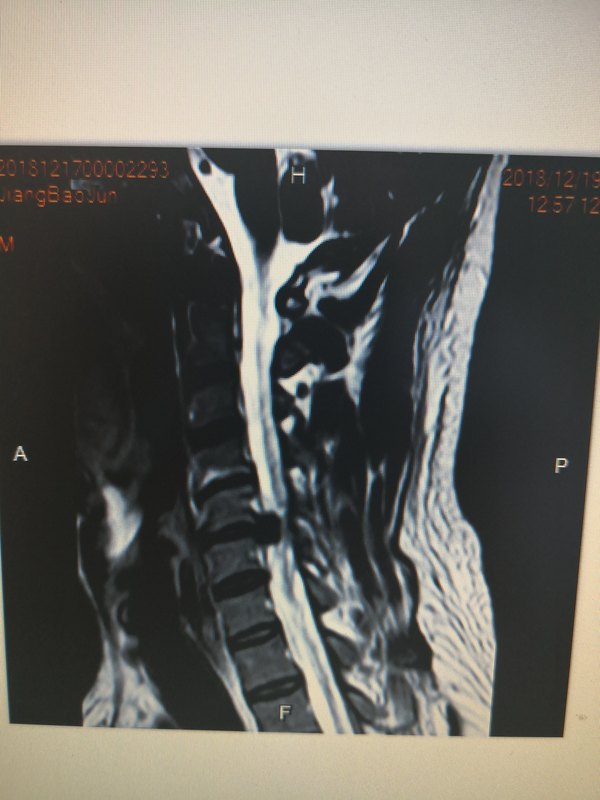

近年來,頸椎病發(fā)病率有逐漸增加的趨勢。由于手機(jī)和電腦的普及,越來越多的年輕人成為“低頭族”, 頸椎病發(fā)病趨向年輕化。 談起頸椎病,哈醫(yī)大二院骨六科夏景君副主任說:頸椎病是是骨科的常見病多發(fā)病。要正確認(rèn)識頸椎病,得先了解一下頸椎的結(jié)構(gòu)。頸椎椎體、椎間盤、椎弓根、關(guān)節(jié)、椎板和韌帶圍成一個(gè)管狀結(jié)構(gòu),使脊髓和神經(jīng)根在里面得到有效保護(hù)。頸椎間盤是連接頸椎之間的纖維結(jié)構(gòu),到一定年齡會發(fā)生退變,再加上一些急慢性損害,如外傷、不良姿勢等,就可能突出,其它結(jié)構(gòu)就可能增生。這些都會導(dǎo)致“管狀結(jié)構(gòu)”變窄,脊髓和神經(jīng)受到壓迫,引起相應(yīng)的癥狀??上攵緳C(jī)、教師、長期應(yīng)用電腦者都是頸椎病的易患人群。頸椎病給生活帶來諸多不便,輕者頸項(xiàng)酸痛,影響生活質(zhì)量;重者可以導(dǎo)致癱瘓,危及生命。 頸椎病臨床分型 臨床上頸椎病分為多種類型,其中以神經(jīng)根型頸椎病發(fā)病率最高。神經(jīng)根型頸椎病主要是增生物壓迫神經(jīng)根引起的一系列癥狀,多表現(xiàn)為頸肩痛,疼痛可放射至上肢、手,并伴有麻木。脊髓型頸椎病則是由于頸椎間盤突出或其他因素壓迫或刺激脊髓及伴行血管而出現(xiàn)脊髓神經(jīng)的感覺、運(yùn)動、反射與排便功能障礙,以四肢無力、雙腿發(fā)緊及抬步沉重感等開始,漸而出現(xiàn)足踏棉花、抬步打漂、步態(tài)拙笨及束胸感等癥狀,后期還可出現(xiàn)排便、排尿功能障礙。對于椎動脈型和交感神經(jīng)型頸椎病,至今仍有爭議。門診常遇到頭暈的患者來骨科就診,其實(shí)頭暈可由多種原因引起,如腦血管疾病、耳石癥、美尼爾綜合征等等,因此,如有頭暈的發(fā)作,應(yīng)先排除其它疾病,先去神經(jīng)內(nèi)科就診,以免延誤病情。 如何預(yù)防頸椎病? 一定要防微杜漸。預(yù)防頸椎病一定要從改變生活中的不良習(xí)慣做起,如久坐低頭、長時(shí)間應(yīng)用電腦手機(jī)等等,都會加劇頸椎的退變。注意端正頭、頸、肩、背的姿勢,盡量要保持頸椎的正直,不要偏頭聳肩、看書時(shí)要正面注視。注意頸肩部保暖,避免頭頸負(fù)重物,避免過度疲勞。活動時(shí)要防止閃、挫傷。 同時(shí)也要加強(qiáng)頸肩部肌肉的鍛煉。長期低頭工作的人士,可以經(jīng)常練習(xí)頸椎操:端坐,全身不動,單頭部運(yùn)動,分別做低頭、抬頭、左轉(zhuǎn)、右轉(zhuǎn)、前伸、后縮;順、逆時(shí)針環(huán)繞動作。進(jìn)行適當(dāng)?shù)膽敉忮憻?,比如游蛙泳,跳廣場舞等,既可緩解疲勞,又能使肌肉發(fā)達(dá),韌度增強(qiáng),有利于頸段脊柱的穩(wěn)定性,增強(qiáng)頸肩順應(yīng)頸部突然變化的能力。 還要避免高枕睡眠的不良習(xí)慣。高枕使頭部前屈,增大下位頸椎的應(yīng)力,有加速頸椎退變的可能。 如何治療頸椎?。?對于僅有頸部癥狀的頸椎病,可以進(jìn)行理療(包括頸部熱敷,紅外線燈治療等)或口服非甾體抗炎藥物(這里需要說明,很多人認(rèn)為止痛藥是“頂藥”,對身體沒有任何好處,還傷肝腎,其實(shí)不然。研究發(fā)現(xiàn),這類藥物是通過減輕無菌性炎癥來止痛,同樣有治療作用,只是不宜長期應(yīng)用。) 對于按摩,夏主任認(rèn)為,因?yàn)轭i部沒有大的肌肉群保護(hù),有些按摩手法粗暴不正規(guī)反倒會加重癥狀,特別是脊髓型頸椎病的患者,不當(dāng)?shù)陌茨ι踔習(xí)鸢c瘓。牽引治療,主要應(yīng)用于神經(jīng)根型頸椎病。切記,脊髓型頸椎病不能牽引治療,會加重病情。所以,無論是牽引還是按摩都應(yīng)該到正規(guī)醫(yī)院的理療科進(jìn)行。 提醒 如果您出現(xiàn)了進(jìn)行性頸脊髓受壓癥狀并經(jīng)臨床檢查或其他特種檢查(MRI、CT檢查等)證實(shí)為頸椎病,那應(yīng)盡快手術(shù)。部分神經(jīng)根型頸椎病經(jīng)保守治療無效,也應(yīng)手術(shù)治療。由于脊髓神經(jīng)一旦發(fā)生變性后,就是不可逆的,所以手術(shù)時(shí)機(jī)是越早越好。頸椎病的患者由于椎管空間狹小,使得脊髓對于外傷耐受能力降低;常有患者的頭頸部受輕微外傷即癱瘓,無法恢復(fù)。經(jīng)過近幾年脊柱外科技術(shù)的發(fā)展,頸椎病手術(shù)引起四肢癱瘓等并發(fā)癥的病例已非常少見。大家不要對手術(shù)抱有偏見,認(rèn)為手術(shù)后必癱的觀點(diǎn)是錯(cuò)誤的。